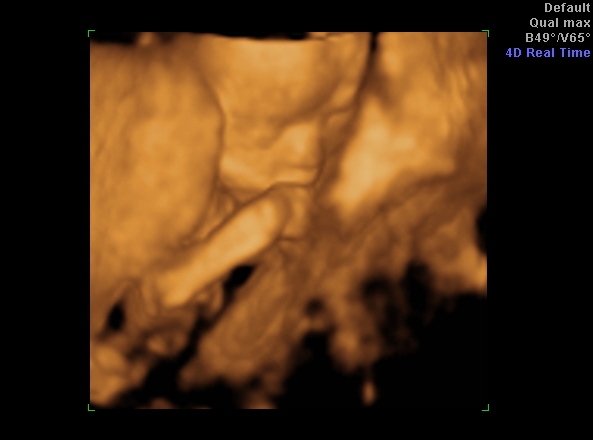

Köszönöm a jobbulás-hozzászólásokat, beváltak, a hasam tök oké végre, csak a babó rugdos óránként (megfordult, most bal oldalt van a feje és jobb oldalt érzem a csikizést